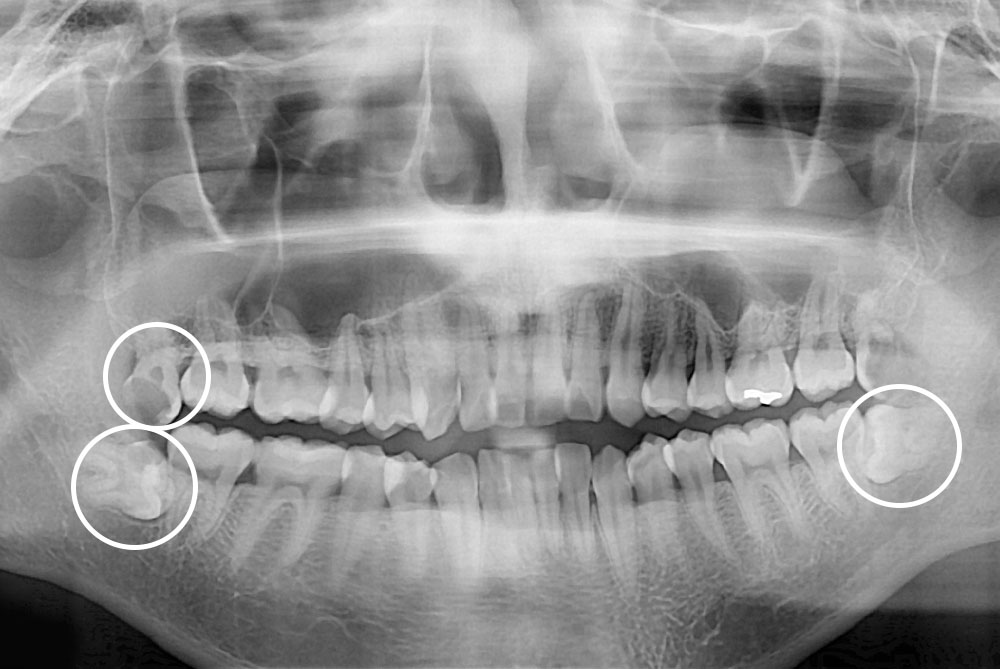

[사랑니] 매복 사랑니 발치

치료전 : 2019-10-10